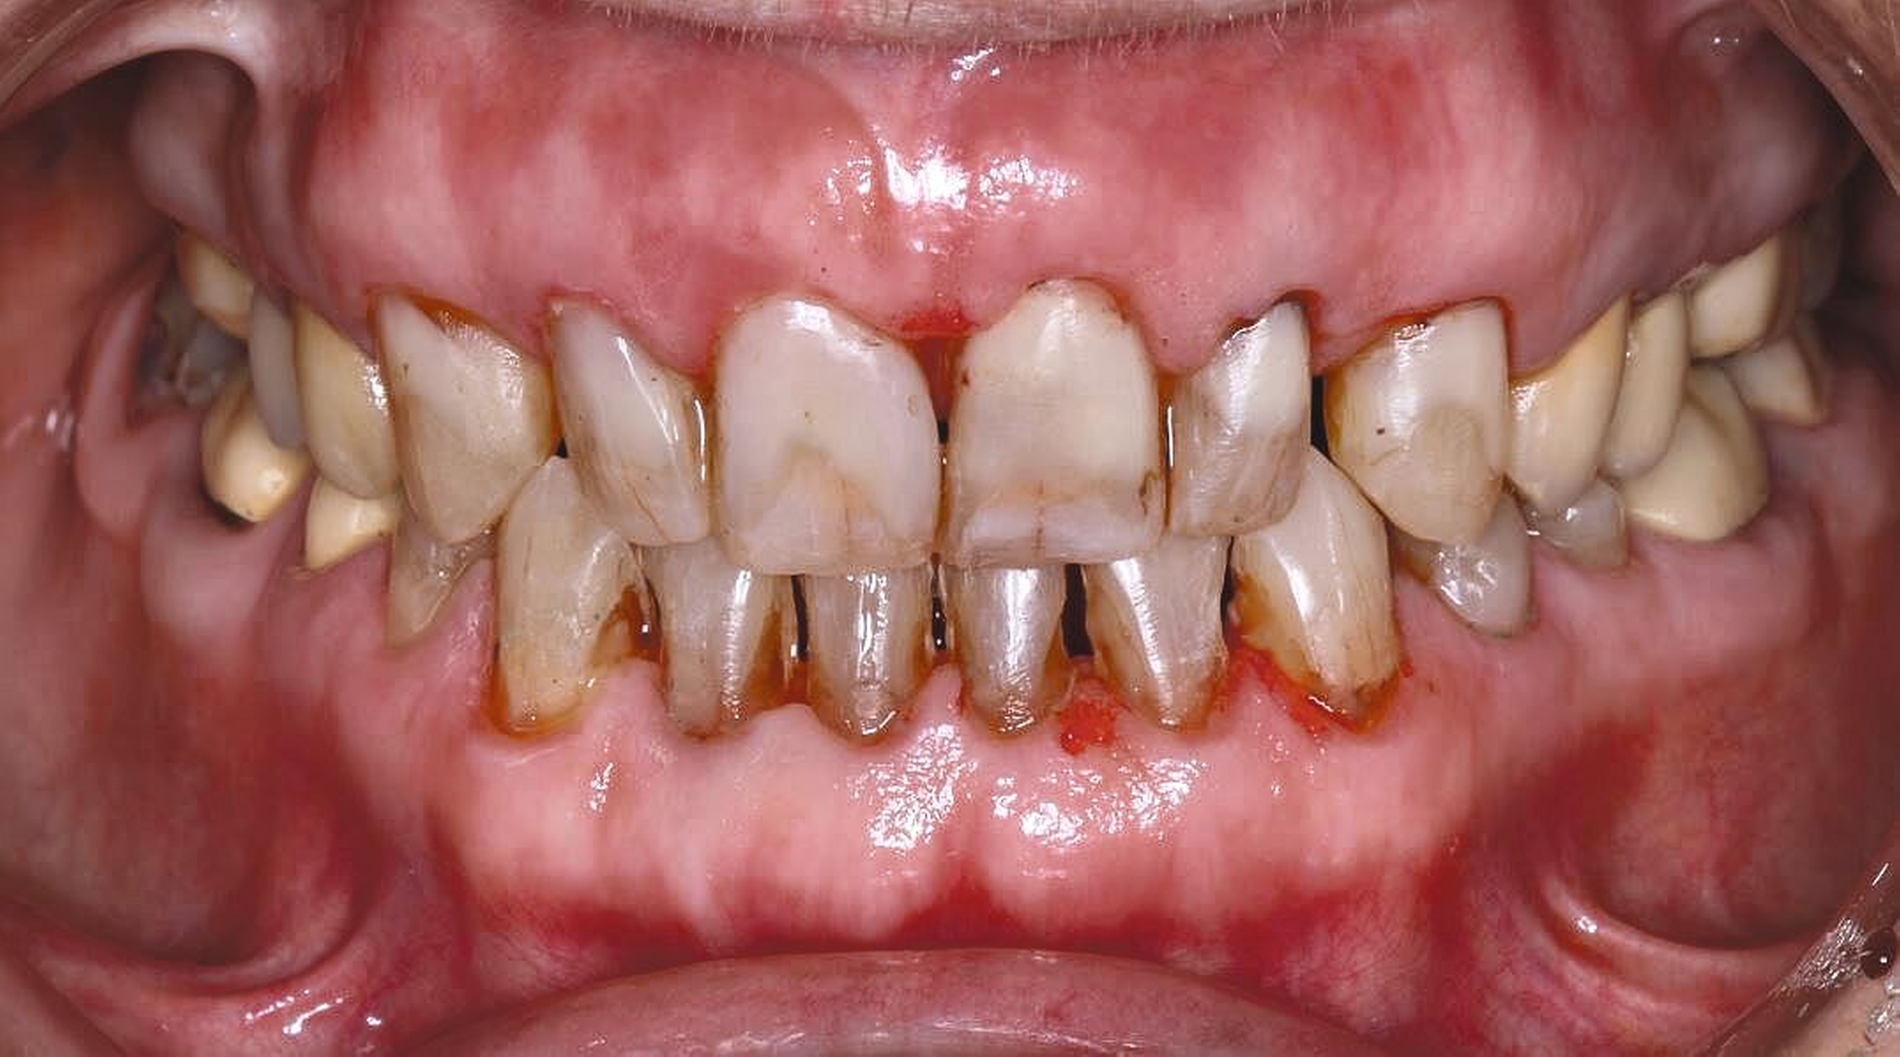

Auch aufseiten der Pflege wurden durch die Einführung des DNQP-Expertenstandards Rahmenbedingungen zur Verbesserung der Mundgesundheit bei Personen mit Pflegebedarf geschaffen. Der Expertenstandard definiert unter anderem das Aufgabenspektrum, den Verantwortungsbereich und das nötige Kompetenzprofil von Pflegefachpersonen in Bezug auf die Mundgesundheit bei Personen mit Pflegebedarf. Als zentrale Anforderung an Pflegefachpersonen formuliert der Expertenstandard zudem die Kompetenz, einschätzen zu können, wann weitere zahnmedizinische Expertise hinzuzuziehen ist [Sirsch et al., 2022]. Um die Maßnahmen zur Förderung der Mundgesundheit nachhaltig zu implementieren, ist ein dauerhafter Austausch zwischen Zahnmedizinern und Pflegeverantwortlichen, unter regelmäßiger Einbeziehung geriatrisch-hausärztlicher Expertise notwendig. Die Telemedizin verspricht in Bezug auf die Verbesserung des Zugangs zu zahnmedizinischen Leistungen für Personen in Pflegeeinrichtungen Zukunftspotenzial [Aquilanti et al., 2020]. Nicht in allen Fällen sind Defizite der Mundhygienefähigkeit absehbar. Nach Unfällen oder Schlaganfällen sind Patientinnen und Patienten eventuell von einem auf den anderen Tag nicht mehr in der Lage, ihre Mundhygiene selbstständig adäquat durchzuführen (Abbildung 4).